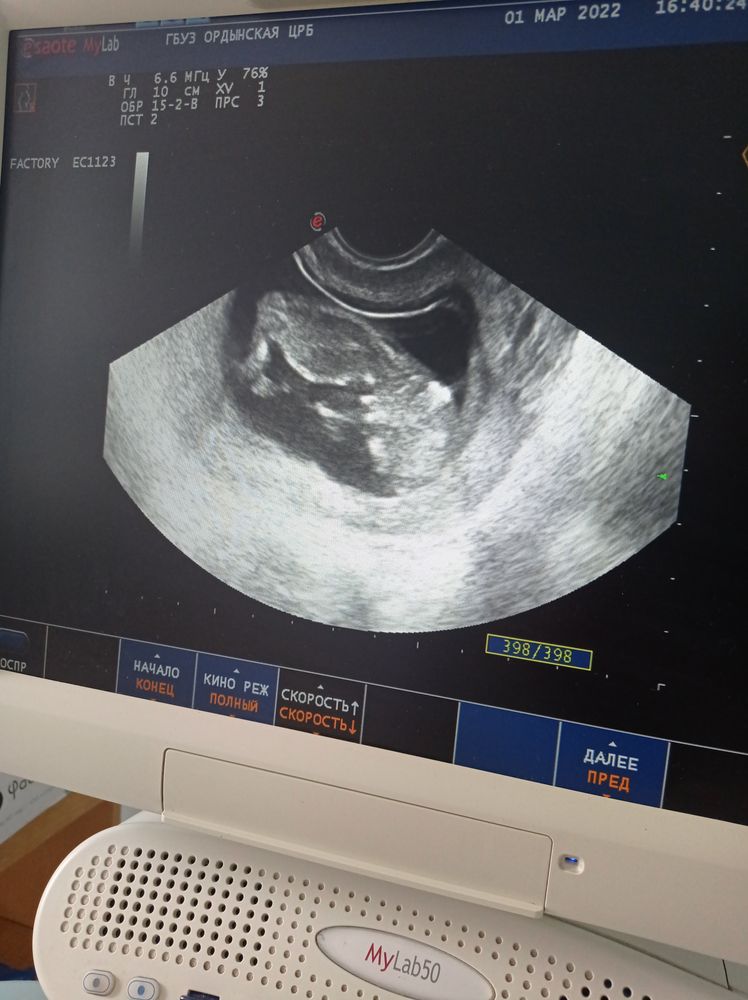

Понимаю, что рано, ходили на УЗИ говорят вроде мальчишка, но возможно и пуповина. Интересно у нас есть шанс на девочку 😂У кого так было? Поделитесь 🌸

На УЗИ снимке наверное не понятно ничего ...

Да, на вашем снимке не видно половой бугорок)) А то, так бы погадала😊

В 12 недель там у них практически одинаково выглядит. Так что Вам всего лишь предположили.